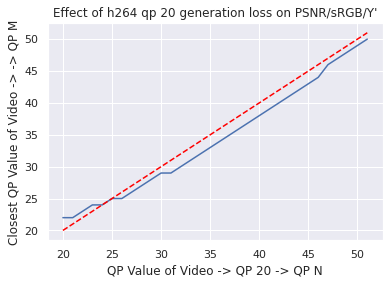

Data: As in [9], our colonoscopy video dataset was collected from screening colonoscopy procedures performed in three hospitals. We used a detector trained on a 16K video subset of the dataset, and we computed our classical codec analyses on a different 80 video subset (2.2M frames, 15K polyp frames). All videos and metadata were deidentified according to the Health Insurance Portability and Accountability Act Safe Harbor. Ground truth polyp labeling was provided by the gastroenterologist annotators described in [9]. The annotators were paid on an hourly basis, and pay was not based on the results they provided. The videos were compressed using H264 QP20 when transmitted from the hospitals. To justify our analyzing already-compressed videos, we used a small number of lossless videos to investigate the impact of re-compressing compressed videos to QP (so called “generation loss"). We found that the impact was negligible (see Appendix for details).

Since our dataset was compressed to be transferred from hospitals, we first investigated the impact of multiple stages of compression ("generation loss"). We used lossless video (24 seconds, 1.4GB) collected from an endoscope viewing dyed, non-human tissue. This gave the video the motion and texture characteristics of a colonoscopy. We then compared video quality between two compression schemes: compressing using H264 QP , where , and compressing to H264 QP20, then to H264 QP (when referring explicitly to this comparison, we will concisely refer to the latter as ’QP’). We then compared the average frame quality between these two schemes using two quality metrics (see ’Metrics’ section). The quality differences between these two compression schemes was minor in terms of PSNR-CbCr, which justifies our working with video data already compressed by H264 QP20.